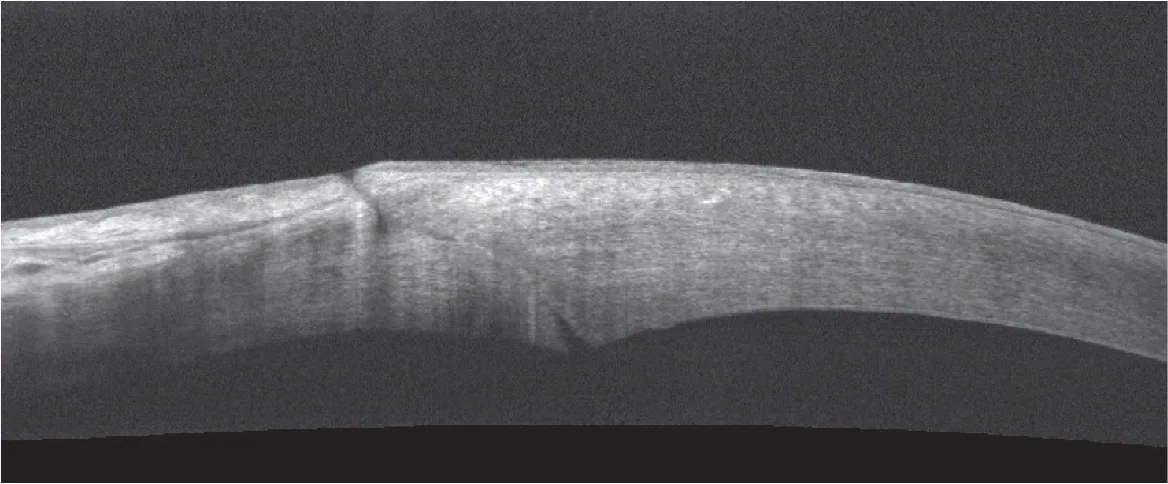

Figure 3.6. Deux constructions incisionnelles différentes en OCT HD : incision directe (2,75 mm) mais tunnelisée (A)

Figure 3.6. Deux constructions incisionnelles différentes en OCT HD : et incision construite (1,8 mm) en trois plans (B).

Figure 3.7. OCT peropératoire de l’incision principale (2,2 mm), juste après réalisation de celle-ci (A)

Figure 3.7. OCT peropératoire de l’incision principale (2,2 mm), et en fi n d’intervention après l’implantation (B).